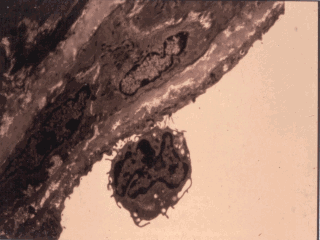

| What might acute phase cytokines do? This slide shows an

effect of cytokine activation of endothelial cells. These cells on stimulation with TNF-alpha,

IL-1, IL-6 expressed number of adhesion molecules causing rolling and the adherence of

lymphocytes which may will be the earliest phases of the formation of fatty streaks in the

atherosclerotic plague. |